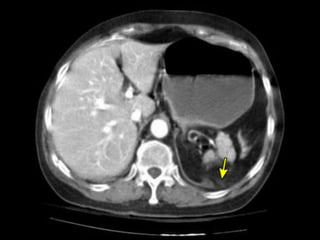

Trauma de Diafragma

 Diagnostico



TC

 Sensibilidad

0% si no existe contendio

herniado (TC contrastada S: 95% en

presencia de herniación)